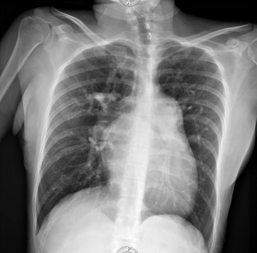

As part of the diagnostic approach for syncope, an electrocardiogram is obtained (Figure 1).1 A chest x-ray is also obtained (Figure 2).

Figure 2 Anteroposterior chest X-ray: elongated arch of the right atrium, elongated pulmonary arch, dilated right ventricle, LUPI index 34 mm, prominence of the right pulmonary bronchus, venous capillary hypertension, absence of pleural effusion.